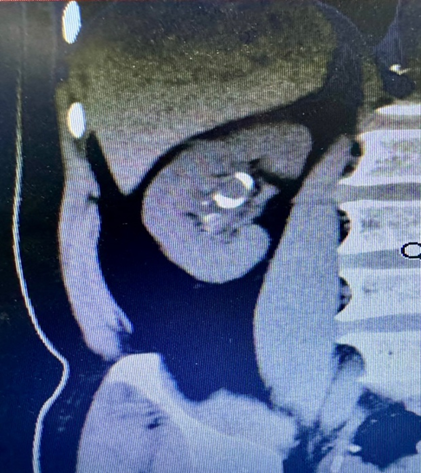

术后CT复查